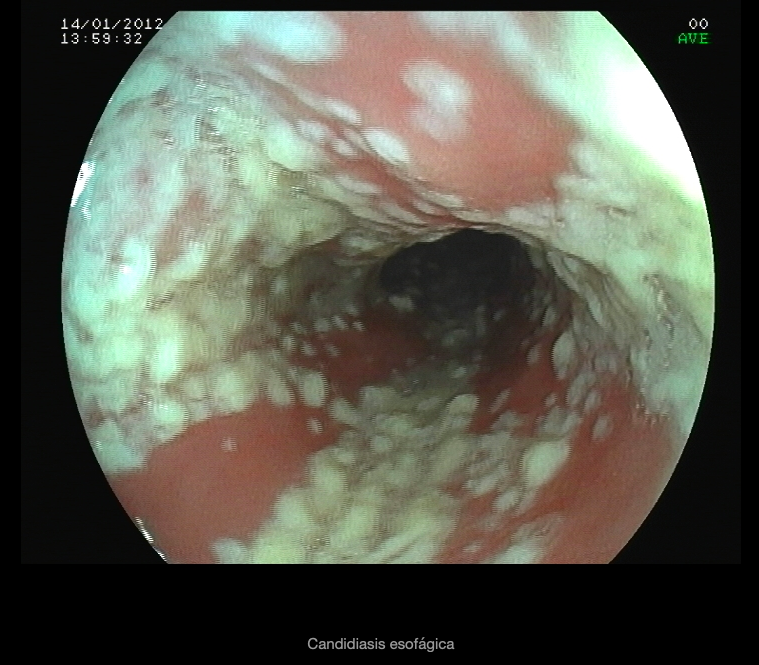

El diagnóstico definitivo generalmente se realiza al hacer una endoscopia, durante la cual se observan lesiones blanquecinas en forma de placas en la mucosa. La biopsia muestra la presencia de levaduras e hifas que invaden las células de la mucosa, y el cultivo revela la presencia de Candida.